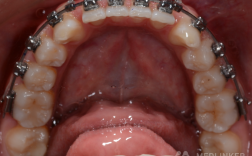

牙齿正畸治疗中,钢丝(专业称“弓丝”)是移动牙齿的核心工具,通过施加持续、轻柔的力量引导牙齿排列整齐、调整咬合关系,许多患者复诊时会问:“每次都要换钢丝吗?”是否更换钢丝、更换何种钢丝,需根据治疗阶段、牙齿移动情况、个体差异等多因素综合判断,并非“一刀切”的流程,下面将从治疗阶段、钢丝作用原理、影响因素等方面详细说明。

正畸钢丝的本质是“记忆金属”,通过自身形态恢复产生的力,推动牙齿在牙槽骨中移动,不同治疗阶段,牙齿移动的目标不同(如排齐、整平、关闭间隙、精细调整),所需钢丝的材质、粗细、形态也各异,换钢丝”的频率和类型会动态调整。

刚戴上矫治器时,牙齿可能存在拥挤、错位,此时需要“轻柔启动”的力量,医生通常会先放入较细的镍钛圆丝(直径0.012-0.014英寸),这种钢丝具有“超弹性”,能持续释放轻柔力量,让牙齿在无明显疼痛的情况下开始移动。

当牙齿初步排齐后,需“整平牙弓”,即让所有牙齿的切缘在同一平面上,解除“深覆颌”“深覆盖”等问题,此时会换成更粗的镍钛圆丝(0.018英寸)或不锈钢圆丝,后者力量更强,能稳定维持已排齐的牙齿位置。

若治疗中需拔除前磨牙(为拥挤牙齿腾出空间),此阶段的目标是“关闭拔牙间隙”,医生会使用不锈钢方丝(如0.018×0.025英寸)或镍钛方丝,配合“关闭曲”“滑动杆”等技术,让牙齿向拔牙隙移动。

当牙齿排列整齐、间隙关闭后,进入“精细调整”阶段,目标是调整牙根角度、改善咬合功能(如避免“地包天”“龅牙”复发),此时会使用较细的不锈钢方丝(0.016×0.022英寸)或记忆钛丝,通过弯制“摇椅形弓丝”“转矩曲”等,对牙根进行三维控制。